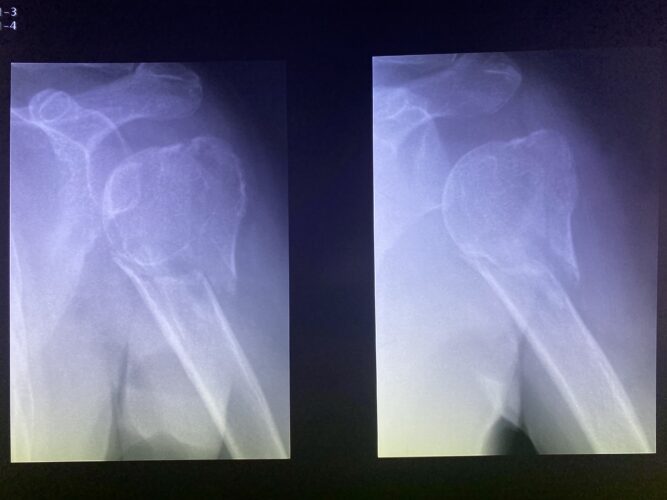

さわやか千葉県民プラザ(肩関節脱臼)

さわやか千葉県民プラザ(上腕骨外科頸骨折)

さわやか千葉県民プラザ(上腕骨外科系骨折)